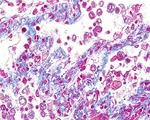

免疫グロブリン 内分泌系

IgG αSMA Desmin Insulin ChromograninA

IgGの染色態度 αSMAの染色態度 Desminの染色態度 Insulinの染色態度 ChromograninAの染色態度